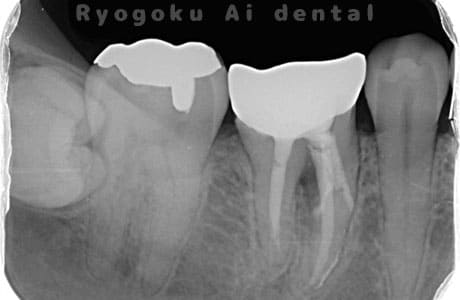

Case05

-

術後2ヶ月

- 原因

- 右下6番近心根パーフォーレーション

- 治療内容

- 外科的パーフォレーションリカバリー治療

- 治療費用

- ¥66,000

右下の奥から2番目の歯に穴が空いており、腫れが引かず、他院で抜歯と診断された患者様です。被せ物を外さずに、穴が空いている部分に外科的にアクセスし、その部分を修復手術を行いました。治療後も再発せず、経過良好です。

<リスク・副作用>

手術後は痛み、腫れ、痺れ、青あざなどの副作用が生じます。痛みは痛み止めを処方しますが、腫れ、青あざは1週間程度生じる場合があります。また、部位によっては神経の走行が複雑で、痺れが残り、長期的にお薬を処方する場合があります。